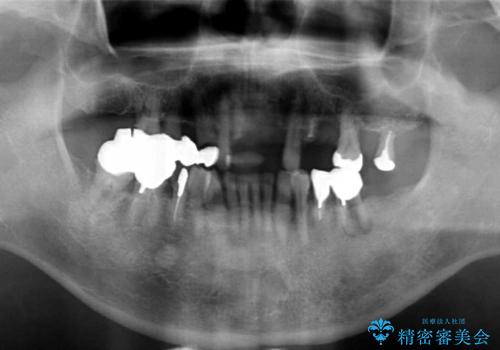

- 交通事故により前歯が折れたことを主訴に来院された患者様です。

精査したところ、前歯以外にも歯が折れており、上の歯の多くが保存不可能な状態でした。

保存可能な2本の歯を用いて、マグネットデンチャー(磁性アタッチメントを用いた入れ歯)による治療を行いました。

- ¥780,000 (根管治療×2本、土台×2本、磁性アタッチメント×2、金属床義歯)費用は治療当時の料金となります